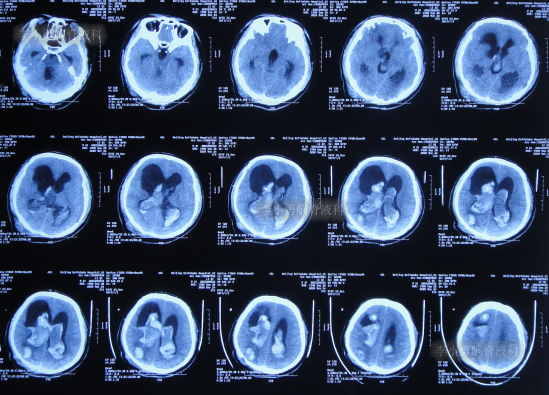

脑室腹腔分流术后2天即2020年5月15日,晚10点出现癫痫发作1次,2分钟左右后自行缓解,查头颅CT示脑室分流术后状态,仍脑积水(图-5)。

图-5:2020年5月15日晚10点半头颅CT

但查头颅CT后1小时,患者头痛加重,且出现呕吐,查头颅CT后示右侧脑室穿刺道出血(图-6)。

图-6:2020年5月15日晚上11点56头颅CT

给予腰穿和储液囊抽吸出血性脑脊液,但治疗4天后效果不理想,患者仍头胀,呕吐,无法进食,精神差,饮食差,晚上睡眠差。期间2次查头颅CT(图-7、图-8)均示积血仍未减少。

图-7:2020年5月17日头颅CT

图-8:2020年5月19日头颅CT